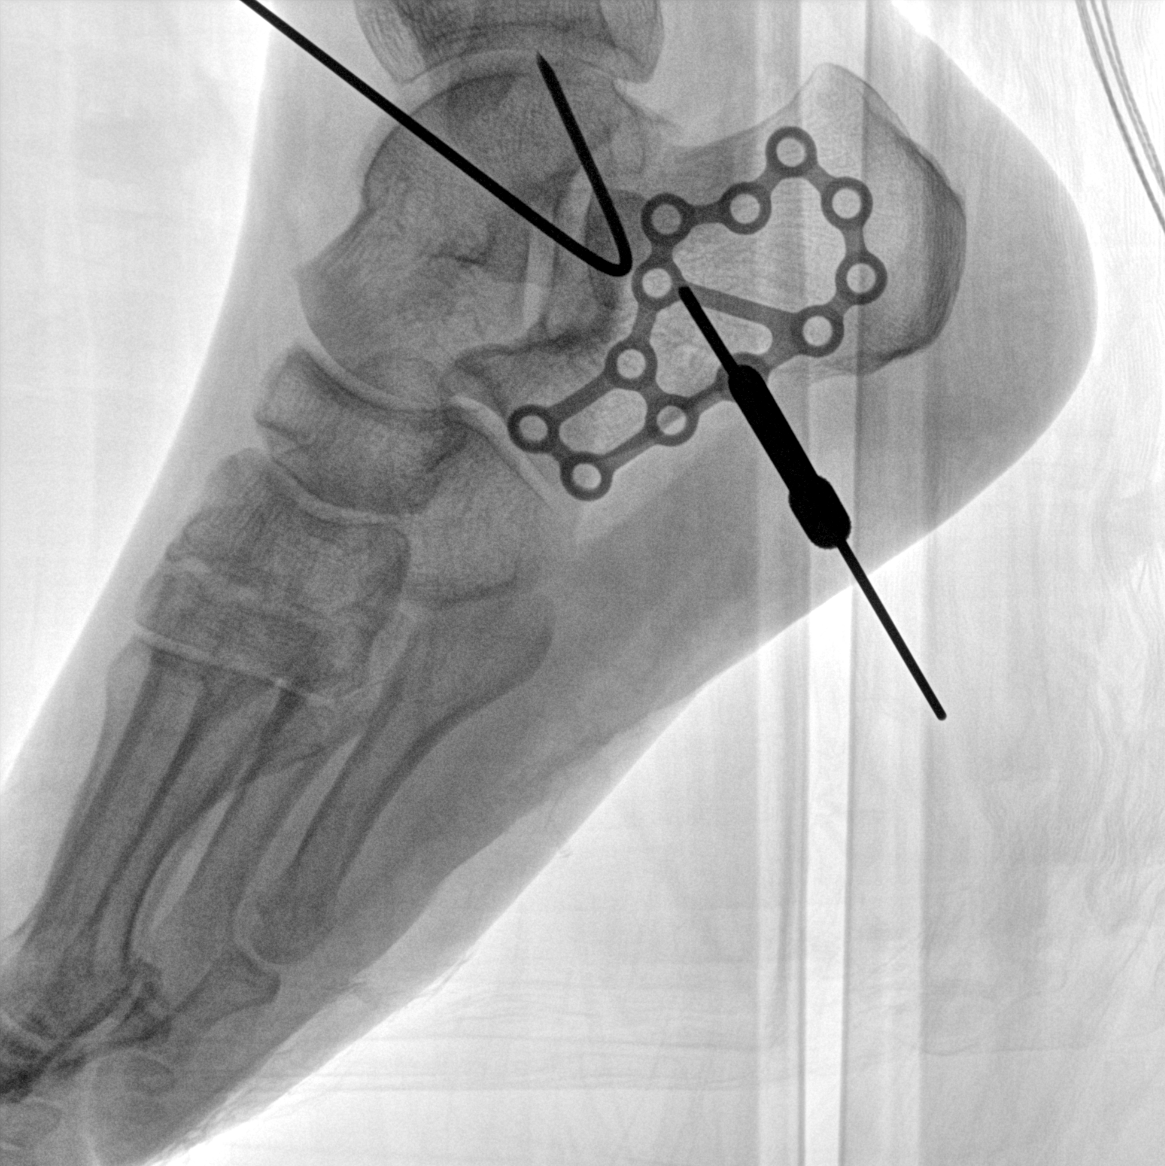

術(shù)中三維成像和橫斷面圖像提供多角度的手術(shù)診斷信息,輔助醫(yī)生進(jìn)行術(shù)中評(píng)估判斷,諸如骨折復(fù)位情況和內(nèi)植入螺釘?shù)某叽绾臀恢?,輔助手術(shù)更好地完成。